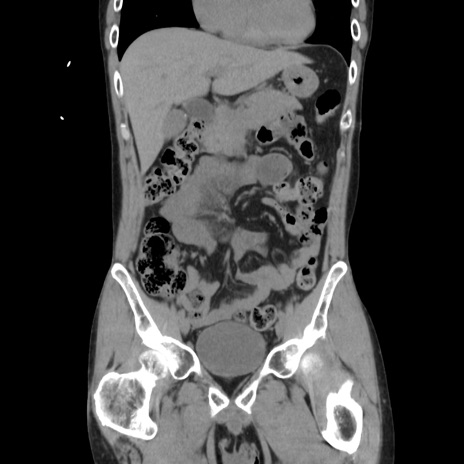

症例37(冠状断像)

【症例】40歳代 男性

【主訴】腹痛

【現病歴】4時間ほど前に電車に乗車中に臍部上より腹痛出現。徐々に増悪し起立困難となり、救急外来受診。生ものは数日食べていない。今朝お雑煮を食べた。

【身体所見】BT 36.8℃、BP 117/84mmHg、HR 91/min、SpO2 97%、苦悶様、腹部:臍上部広範囲圧痛あり、反跳痛±

【データ】WBC 8100、CRP 0.03